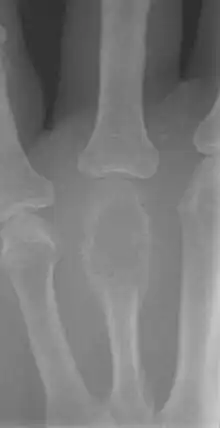

The most common bone tumor is a non-ossifying fibroma.[4] Average five-year survival in the United States after being diagnosed with bone and joint cancer is 67%.[5] The earliest known bone tumor was an osteosarcoma in a foot bone discovered in South Africa, between 1.6 and 1.8 million years ago.[6]

Primary bone tumors

Primary tumors of bone can be divided into benign tumors and cancers. Common benign bone tumors may be neoplastic, developmental, traumatic, infectious, or inflammatory in etiology. Some benign tumors are not true neoplasms, but rather, represent hamartomas, namely the osteochondroma. The most common locations for many primary tumors, both benign and malignant include the distal femur and proximal tibia (around the knee joint). Examples of benign bone tumors include osteoma, osteoid osteoma, osteochondroma, osteoblastoma, enchondroma, giant cell tumor of bone and aneurysmal bone cyst.